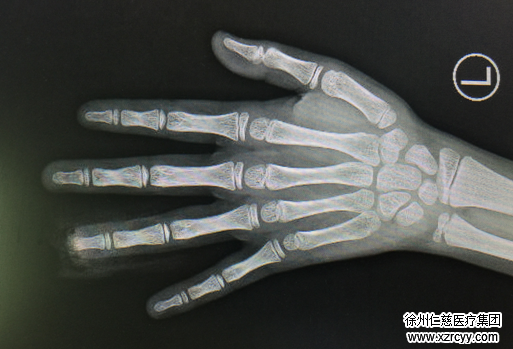

11月12日晚上6点多钟,家住铜山区大许镇的12岁男童航航(化名)正独自在家,眼看到了该吃饭的时间,航航便想着用压面机压点面条吃。结果,航航一只手把面往压面机里塞,而另一只手疯狂地刷着抖音小视频,就在航航把全部精力集中在刷抖音视频上的时候,危险发生了,他的左手环指被绞进压面机,指尖当场被切断。

航航在家人的陪同下第一时间赶往必威官方首页官网betway,接诊的手外科二病区孙传伟医生检查发现,患者左环指指端已完全离断,为了最大可能恢复伤指功能,孙医生手术小组立即为患者实施了V-Y推移皮瓣修复术,最大程度保留原有长度,随后又进行了甲床修复。